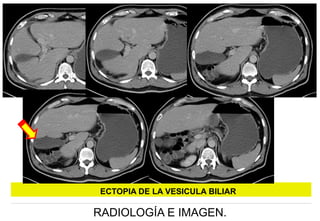

ECTOPIA DE LA VESICULA BILIAR